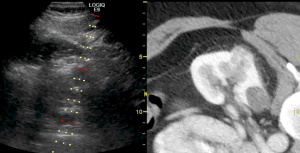

Our section performs and interprets the entire gamut of advanced diagnostic abdominal and pelvic imaging across multiple modalities, including computed tomography (CT), magnetic resonance imaging (MRI), ultrasound, radiography, and fluoroscopy. Our protocols are all encompassing and wide-ranging, including both common and organ-specific complex indications for medical imaging. This includes complete oncologic diagnosis and staging, inflammatory bowel disease, trauma evaluation, emergency radiology, transplant evaluations (such as liver, kidney, pancreas, and bowel), post-operative assessment, genitourinary and reproductive imaging, placental and fetal imaging, CT colonography, contrast enhanced ultrasound, and 3D imaging.

We also perform numerous interventional procedures across the entire body including image-guided minimally invasive biopsies of major solid organs. We have a robust solid organ and soft tissue ablation program with expertise in a wide variety of techniques including microwave ablation, radiofrequency ablation, cryoablation, ethanol ablation, and histotripsy. We also perform fluid aspirations and drainages, including thoracentesis and paracentesis